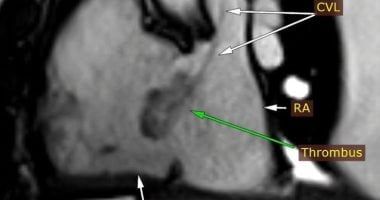

وأضاف الدكتور مجدي القاضي عميد كلية الطب البشري ورئيس مجلس اداره المسشفيات الجامعيه ان التقرير الطبي اوضح بعد إجراء فحوصات الإيكو للقلب، تبين اشتباه وجود ورم بالأذين الأيمن وعلى الفور تم تحويل المريض الى وحدة التصوير الطبى للقلب واجراء رنين مغناطيسى على القلب وتبين ان المريض يعانى من التهابات بعضلة القلب وتواجد جلطة بالاذين الايمن وتم تشخيص الحالة بدقة وتلقى العلاج المناسب بقسم امراض القلب والاوعيه الدمويه.

موكدا، أن الوحدة تعد الأولى من نوعها في إقليم الصعيد، حيث أن هذه الحالة تُعد نموذجًا لما تقدمه وحدة تصوير القلب من خدمات تشخيصية متقدمة، إذ تمكنت من تحديد طبيعة الجلطة ومكانها بدقة عالية، ما ساعد الفريق الطبي في وضع خطة علاج مناسبة أنقذت حياة المريض.